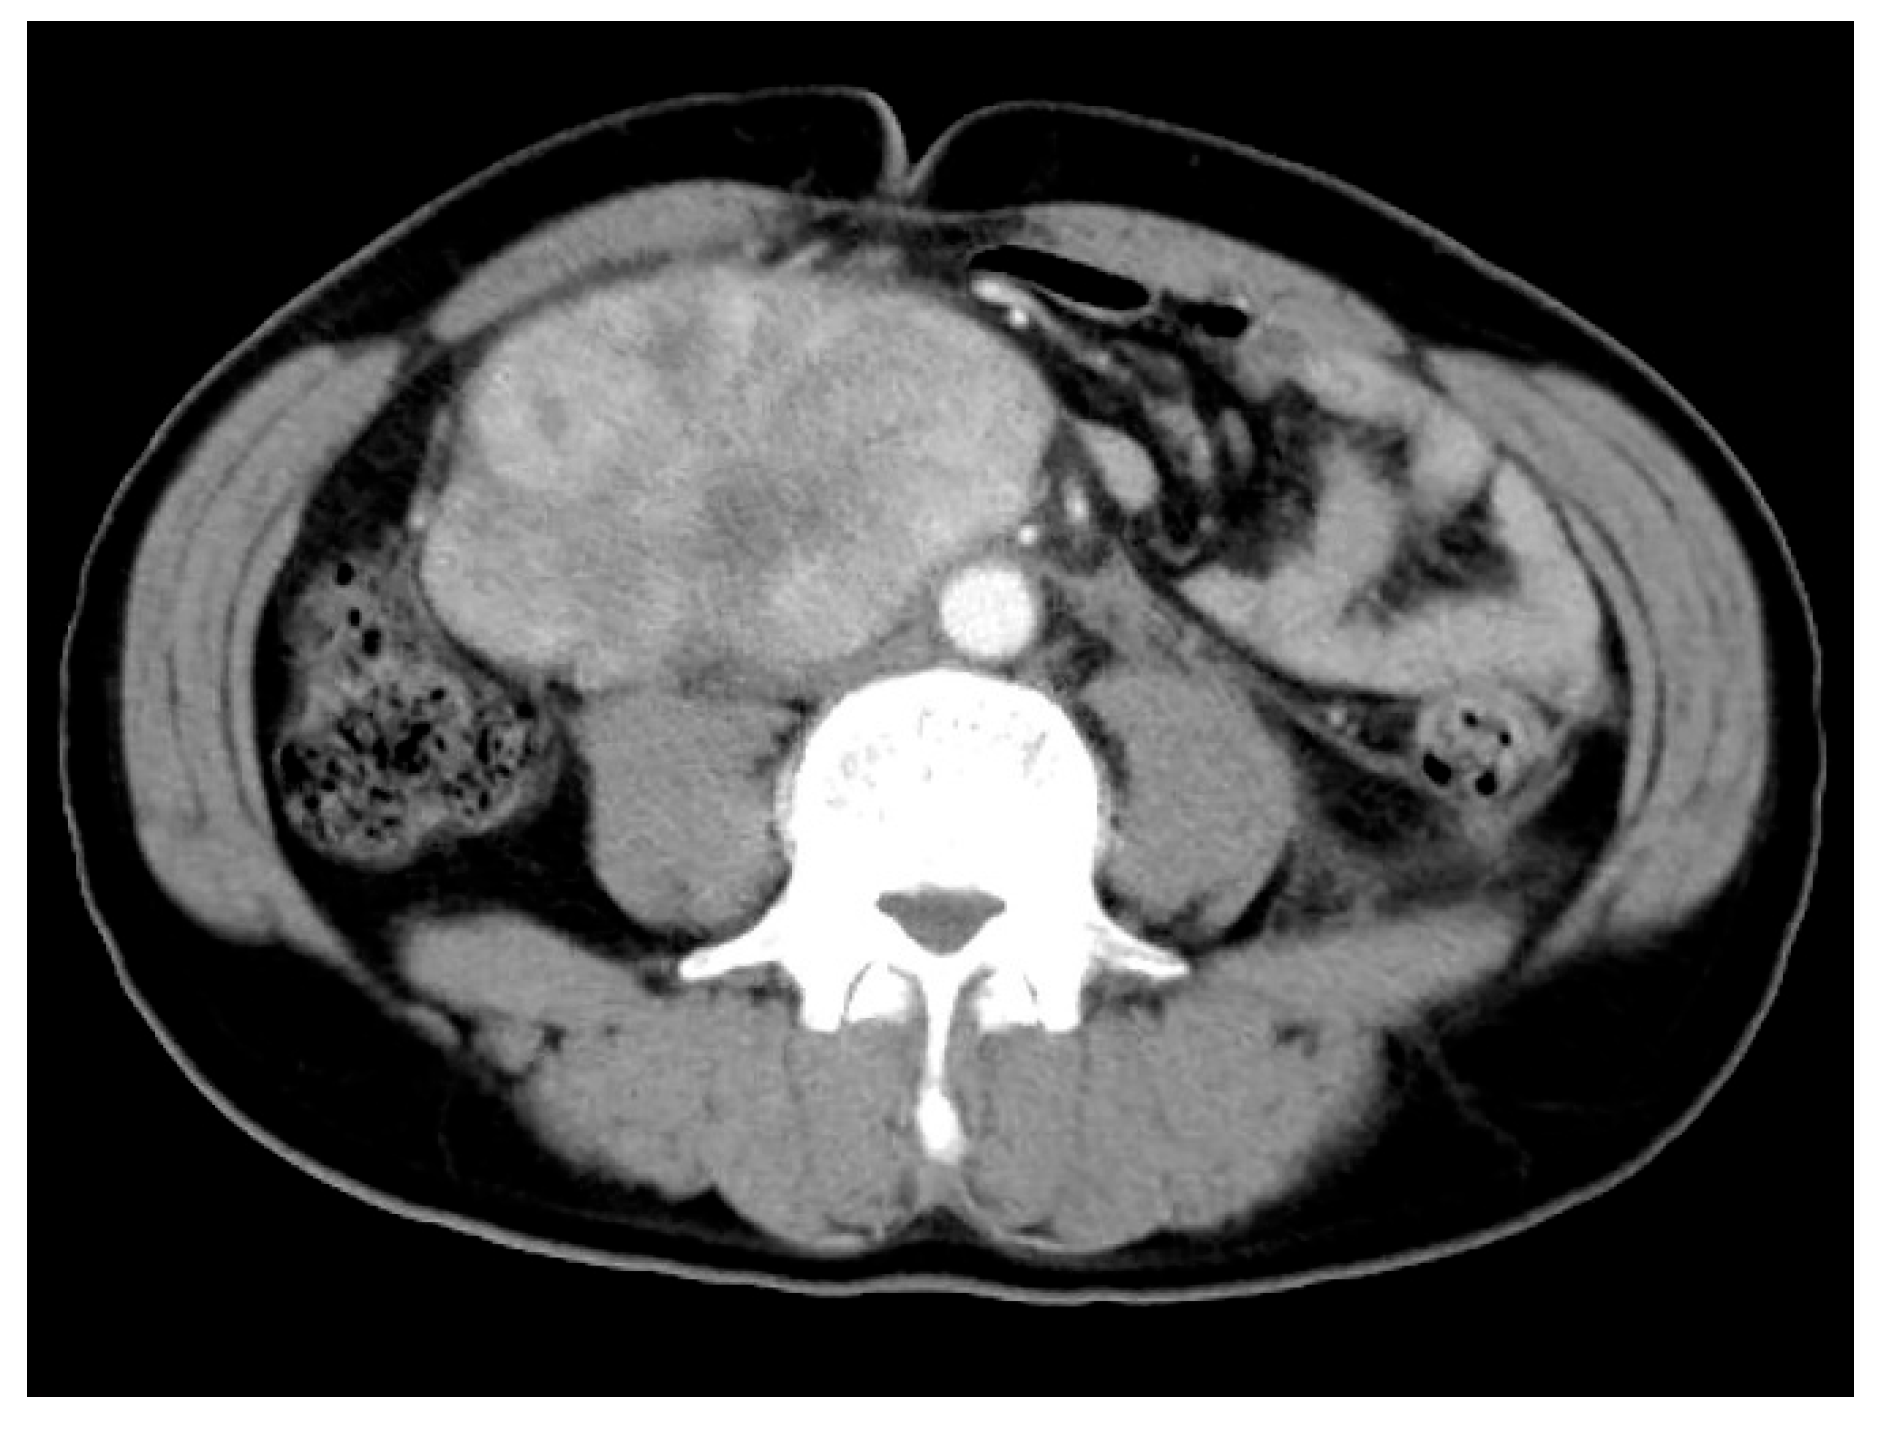

3.2. Radiological Features